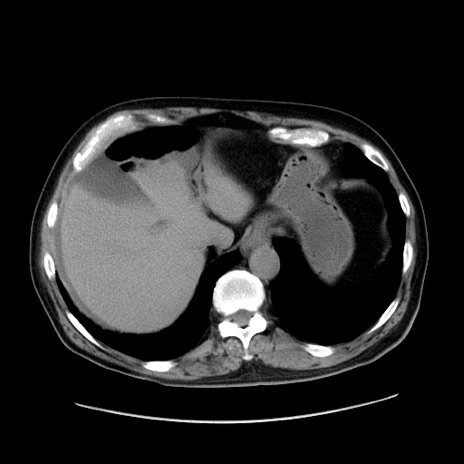

冠状断像

症例30(横断像)

【症例】80歳代男性

【主訴】臍周囲痛

【現病歴】約6時間前から臍下部痛が出現。次第に腹部膨隆・背部痛も生じてきたため来院。背部痛の場所は変化しない。

【既往歴】腎盂腎炎

【身体所見】意識清明、BT 36.3℃、BP  131/87mmHg、P 87bpm、SpO2 100%(RA)、臍周囲自発痛・圧痛あり、反跳痛なし、自発痛部位に一致して板状硬あり、腹部膨隆、腸雑音減弱、CVA tenderness両側陰性。

【データ】WBC 19600、CRP 0.33